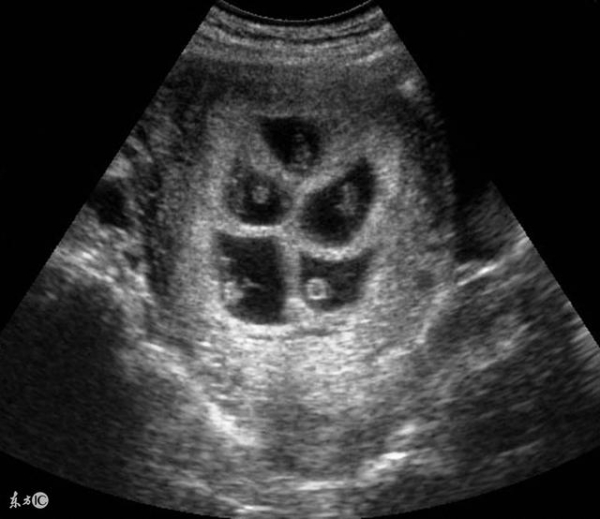

幸運的是,那天早上醒來小雅突然覺得一陣噁心,非常想吐,心想不會是懷上了吧?趕緊去醫院檢查,果真懷上了,這就好像人在沙漠行走遇到綠洲一樣,讓一家子樂壞了!懷孕三月去產檢,醫生滿臉喜悅告知小雅懷的是6胞胎!

夫妻倆都不相信,再三問醫生會不會搞錯,醫生讓其再檢查,真的懷了6胞胎!原來寶寶不是不到,而是遲來的幸運!

生產當天,產科醫生就來了10多名,經過長時間的剖腹手術,小雅順利產下6名可愛的寶寶,主刀醫生看到孩子性別都感嘆:「竟然是3對龍鳳胎,這才是真正的金六福,2018年一大喜!」